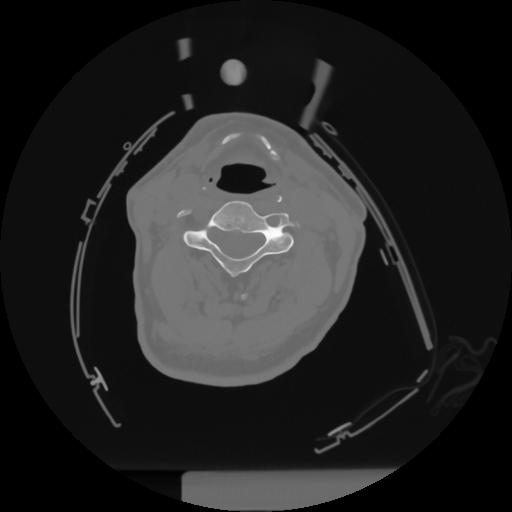

12 P.BLANDAS,,Vol,0.5,P.BLANDAS,,